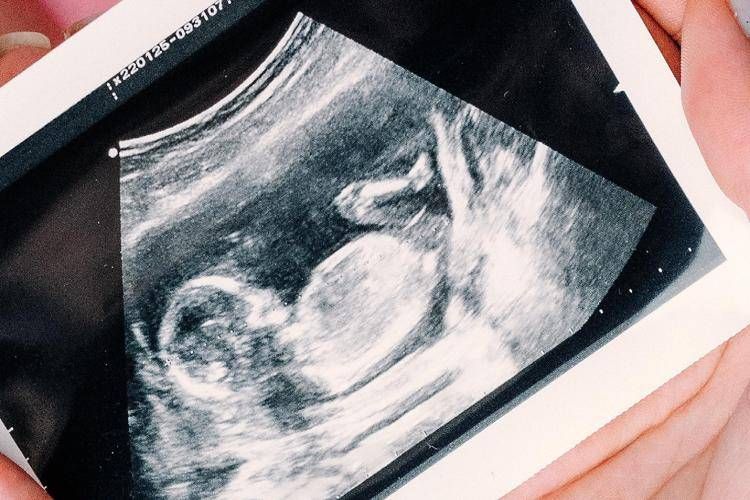

Sì all'ecografia nel primo trimestre per individuare precocemente eventuali malformazioni fetali, oltre a quella già raccomandata nel secondo trimestre. Sì anche all'offerta dello screening nel primo trimestre delle anomalie cromosomiche più frequenti, tra cui la sindrome di Down, mediante test combinato o test del Dna fetale, da proporre a tutte le donne indipendentemente dall'età. Raccomandata l'esecuzione della misura della distanza tra fondo dell'utero e sinfisi pubica ad ogni bilancio di salute a partire dalle 24 settimane gestazionali per valutare l'accrescimento fetale. Rimane non raccomandata l'ecografia nel terzo trimestre, salvo specifica indicazione clinica. Sono queste le principali novità introdotte dalla terza parte dell'aggiornamento della linea guida 'Gravidanza fisiologica', presentata durante un webinar a cura dell'Istituto superiore si sanità, al quale si sono iscritti 850 professionisti sanitari. Il documento è stato sviluppato dal Centro nazionale per la prevenzione delle malattie e la promozione della salute (Cnapps) dell'Iss, nell'ambito delle attività del Sistema nazionale linee guida (Snlg).

La possibilità di individuare già nel primo trimestre eventuali malformazioni consente alla donna e al partner di prepararsi consapevolmente alla nascita, valutare eventuali terapie intrauterine, programmare il parto in strutture adeguate alle necessità assistenziali neonatali o decidere per una interruzione volontaria della gravidanza, spiega l'Iss. "L'ecografia è uno strumento straordinario che ha rivoluzionato l'assistenza ostetrica. Tuttavia, non tutto ciò che è tecnicamente possibile è clinicamente appropriato e non tutto ciò che rassicura è realmente necessario", afferma Serena Donati, responsabile scientifica dell'aggiornamento. "In Italia si eseguono in media 6 ecografie in gravidanza, senza differenze tra gravidanze fisiologiche e patologiche: ben oltre quelle raccomandate dalle linee guida nazionali e internazionali. Quando la pratica clinica si discosta dalle evidenze scientifiche - sottolinea - è fondamentale spiegare con chiarezza alle donne quali siano le indicazioni appropriate agli esami e, quando opportuno, avere il coraggio di dire che non sono necessari. Le linee guida rappresentano una bussola istituzionale per garantire qualità dell'assistenza, equità di accesso alle cure e sostenibilità del Servizio sanitario nazionale".

Tra le principali novità dell'aggiornamento, la linea guida: raccomanda l'ecografia del primo trimestre per la diagnosi precoce di malformazioni fetali e per una corretta datazione della gravidanza; conferma l'offerta universale dello screening nel primo trimestre delle anomalie cromosomiche più comuni, introducendo l’esame del Dna fetale; sottolinea l'importanza del counselling, per rispondere in modo completo e trasparente ai bisogni informativi delle donne rispetto agli accertamenti per anomalie congenite; ribadisce il valore della percezione dei movimenti fetali come indicatore del benessere del feto; raccomanda la misurazione della lunghezza fondo-sinfisi come monitoraggio per la crescita fetale dopo la 24esima settimana; raccomanda di limitare ai soli casi con indicazione clinica l'ecografia per la valutazione della crescita fetale nel terzo trimestre.